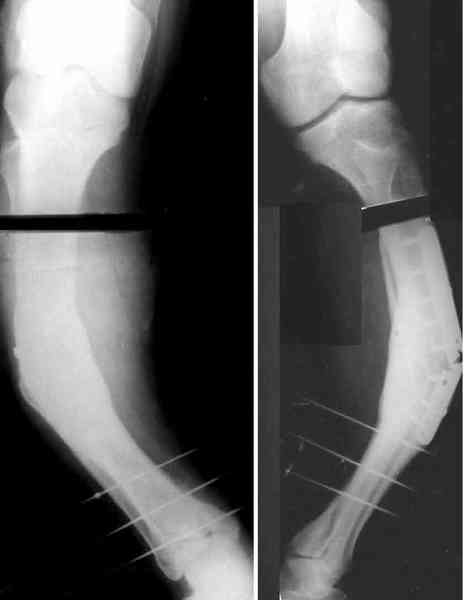

Для продолжения темы - несколько картинок.

Пациент 30 лет, лет пять назад оперирован по поводу перелома голени пластиной. Находясь на героине, нарушил режим, пошел, сломал и ногу и

пластину, но перелом сросся.

В приложении - внешний вид и рентген.

Мнения?

Александр, как раз уровень остеотомии подробнее - на вершине деформации? Там Сломанная пластина.

Там не винты (может, плохо видно), а сломанная пластина, вросшая в кость.

Пластинку и винты мне удалось разглядеть только на профильной проекции, точнее, трехчетвертной, судя по виду коленного сустава (правый снимок). На фасной - вообще не могу разобрать, где она :( Но, в конце концов, можно и не видя ее сказать, что уровень остеотомии может быть и другим, ниже или выше пластинки, придется только компенсировать смещение по ширине, которое появится при полном устранении угла не на вершине.